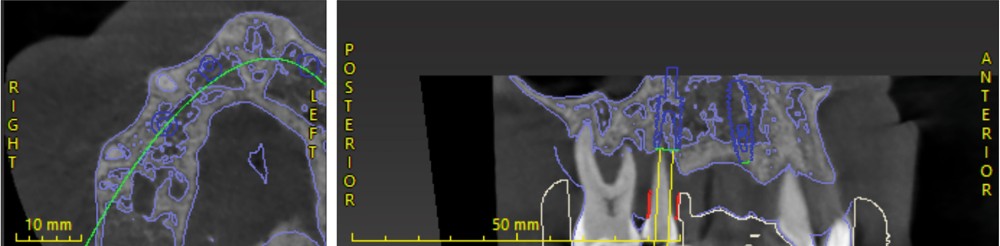

L’empreinte optique, les photographies et le CBCT ont permis une fusion précise des données numériques pour planifier les axes et positions implantaires en fonction du projet prothétique final (fig. 3, 4).

Cette planification a ainsi intégré la future ligne d’émergence et la gestion anticipée des tissus mous [2].